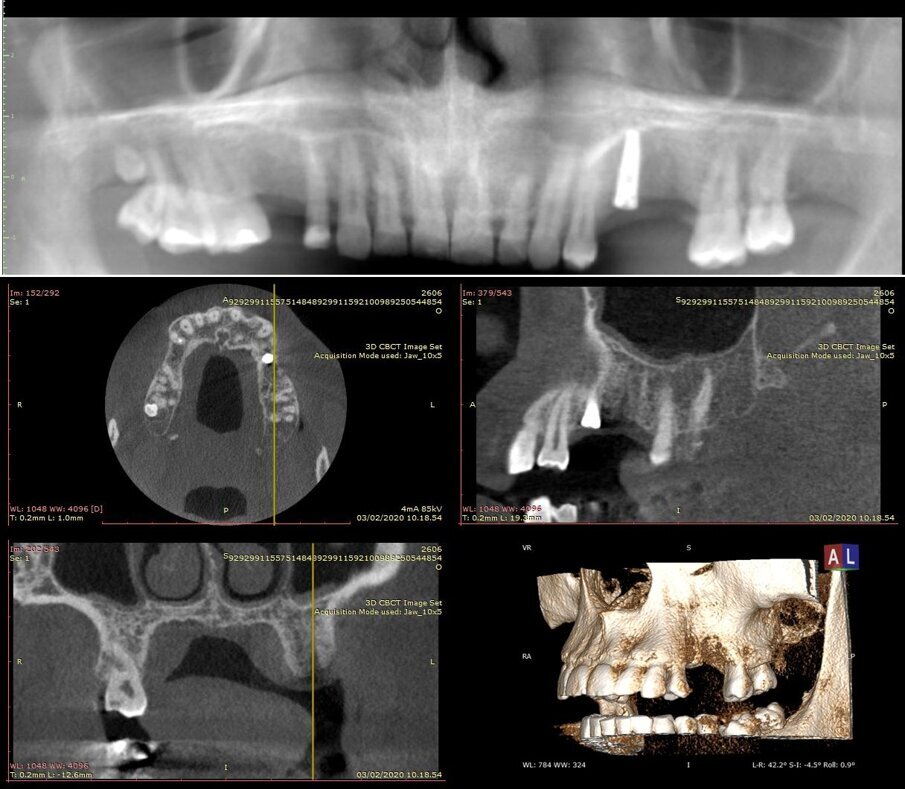

Il paziente R.V. di anni 40 affetto da Neurofibromatosi di tipo I, non fumatore e con neurofibroma palatino è reduce da intervento di avulsione dell’elemento 2.6 e cistectomia con concomitante socket preservation a cielo coperto ed inserimento sempre contestuale di impianto 2.5 in tecnica navigata; necessita per il completamento della riabilitazione dell’emiarcata superiore sinistra dell’inserimento di un secondo impianto in zona 2.6 (Figg. 1a, 1b). La ceratura diagnostica digitale evidenzia, già nel primo intervento, un importante compromesso estetico- igienico accettato dal paziente in virtù della firbomatosi da cui è affetto che ha scoraggiato qualsiasi procedura invasiva (un’esperienza personale nel trattamento del padre riporta un sanguimento difficilmente controllabile della mucosa affetta in corso di chirurgia a cielo aperto ed una guarigione dei tessuti particolarmente imprevedibile anche quando cheratinizzati; nulla è stato trovato al riguardo in letteratura). (Fig. 2).

Figg. 1a, 1b - Situazione iniziale.